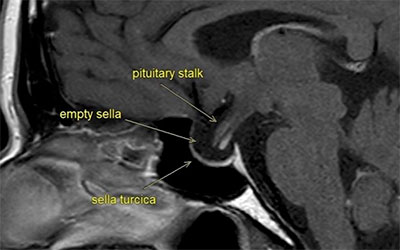

กลุ่มอาการเซลลาว่างเปล่า หรือ ESS เป็นภาวะที่ตรวจพบว่าบริเวณ “sella turcica” ซึ่งเป็นโพรงกระดูกบริเวณฐานสมองที่บรรจุต่อมใต้สมอง (pituitary gland) มีลักษณะดู “ว่างเปล่า” หรือมีเนื้อเยื่อของต่อมใต้สมองแบนลงไปจากแรงดันของน้ำไขสันหลัง ทำให้ดูเหมือนไม่มีต่อมใต้สมองอยู่ในโพรงนั้นเมื่อดูจากภาพถ่าย MRI หรือ CT scan

• MRI สมอง – เป็นการตรวจที่แม่นยำที่สุด พบโพรง sella turcica ขยายและมีน้ำไขสันหลังเข้าไปแทนที่ เนื้อเยื่อต่อมใต้สมองแบนราบชิดผนัง